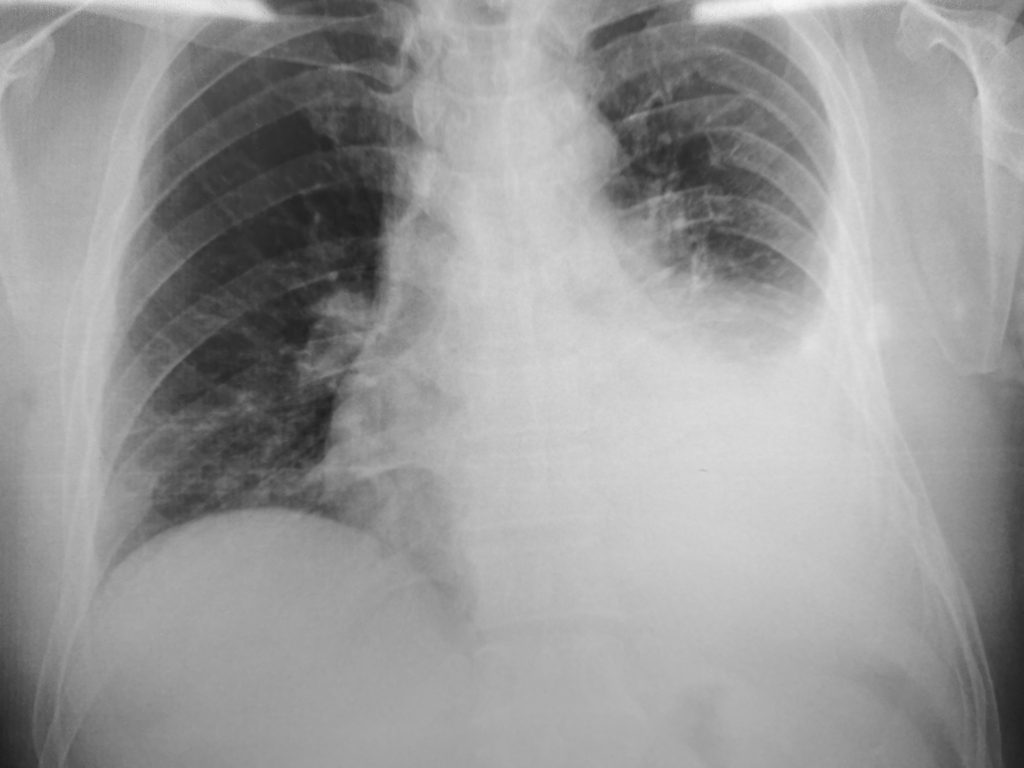

A pleural effusion is a buildup of extra fluid in the space between the lungs and the chest wall, known as the pleural space. This fluid can compress the lung, leading to symptoms such as shortness of breath, chest discomfort, and/or a cough. It’s a symptom of an underlying condition, not a disease itself.

- Imaging: We use imaging tests like a chest X-ray, ultrasound, or CT scan to locate the fluid and assess its volume.